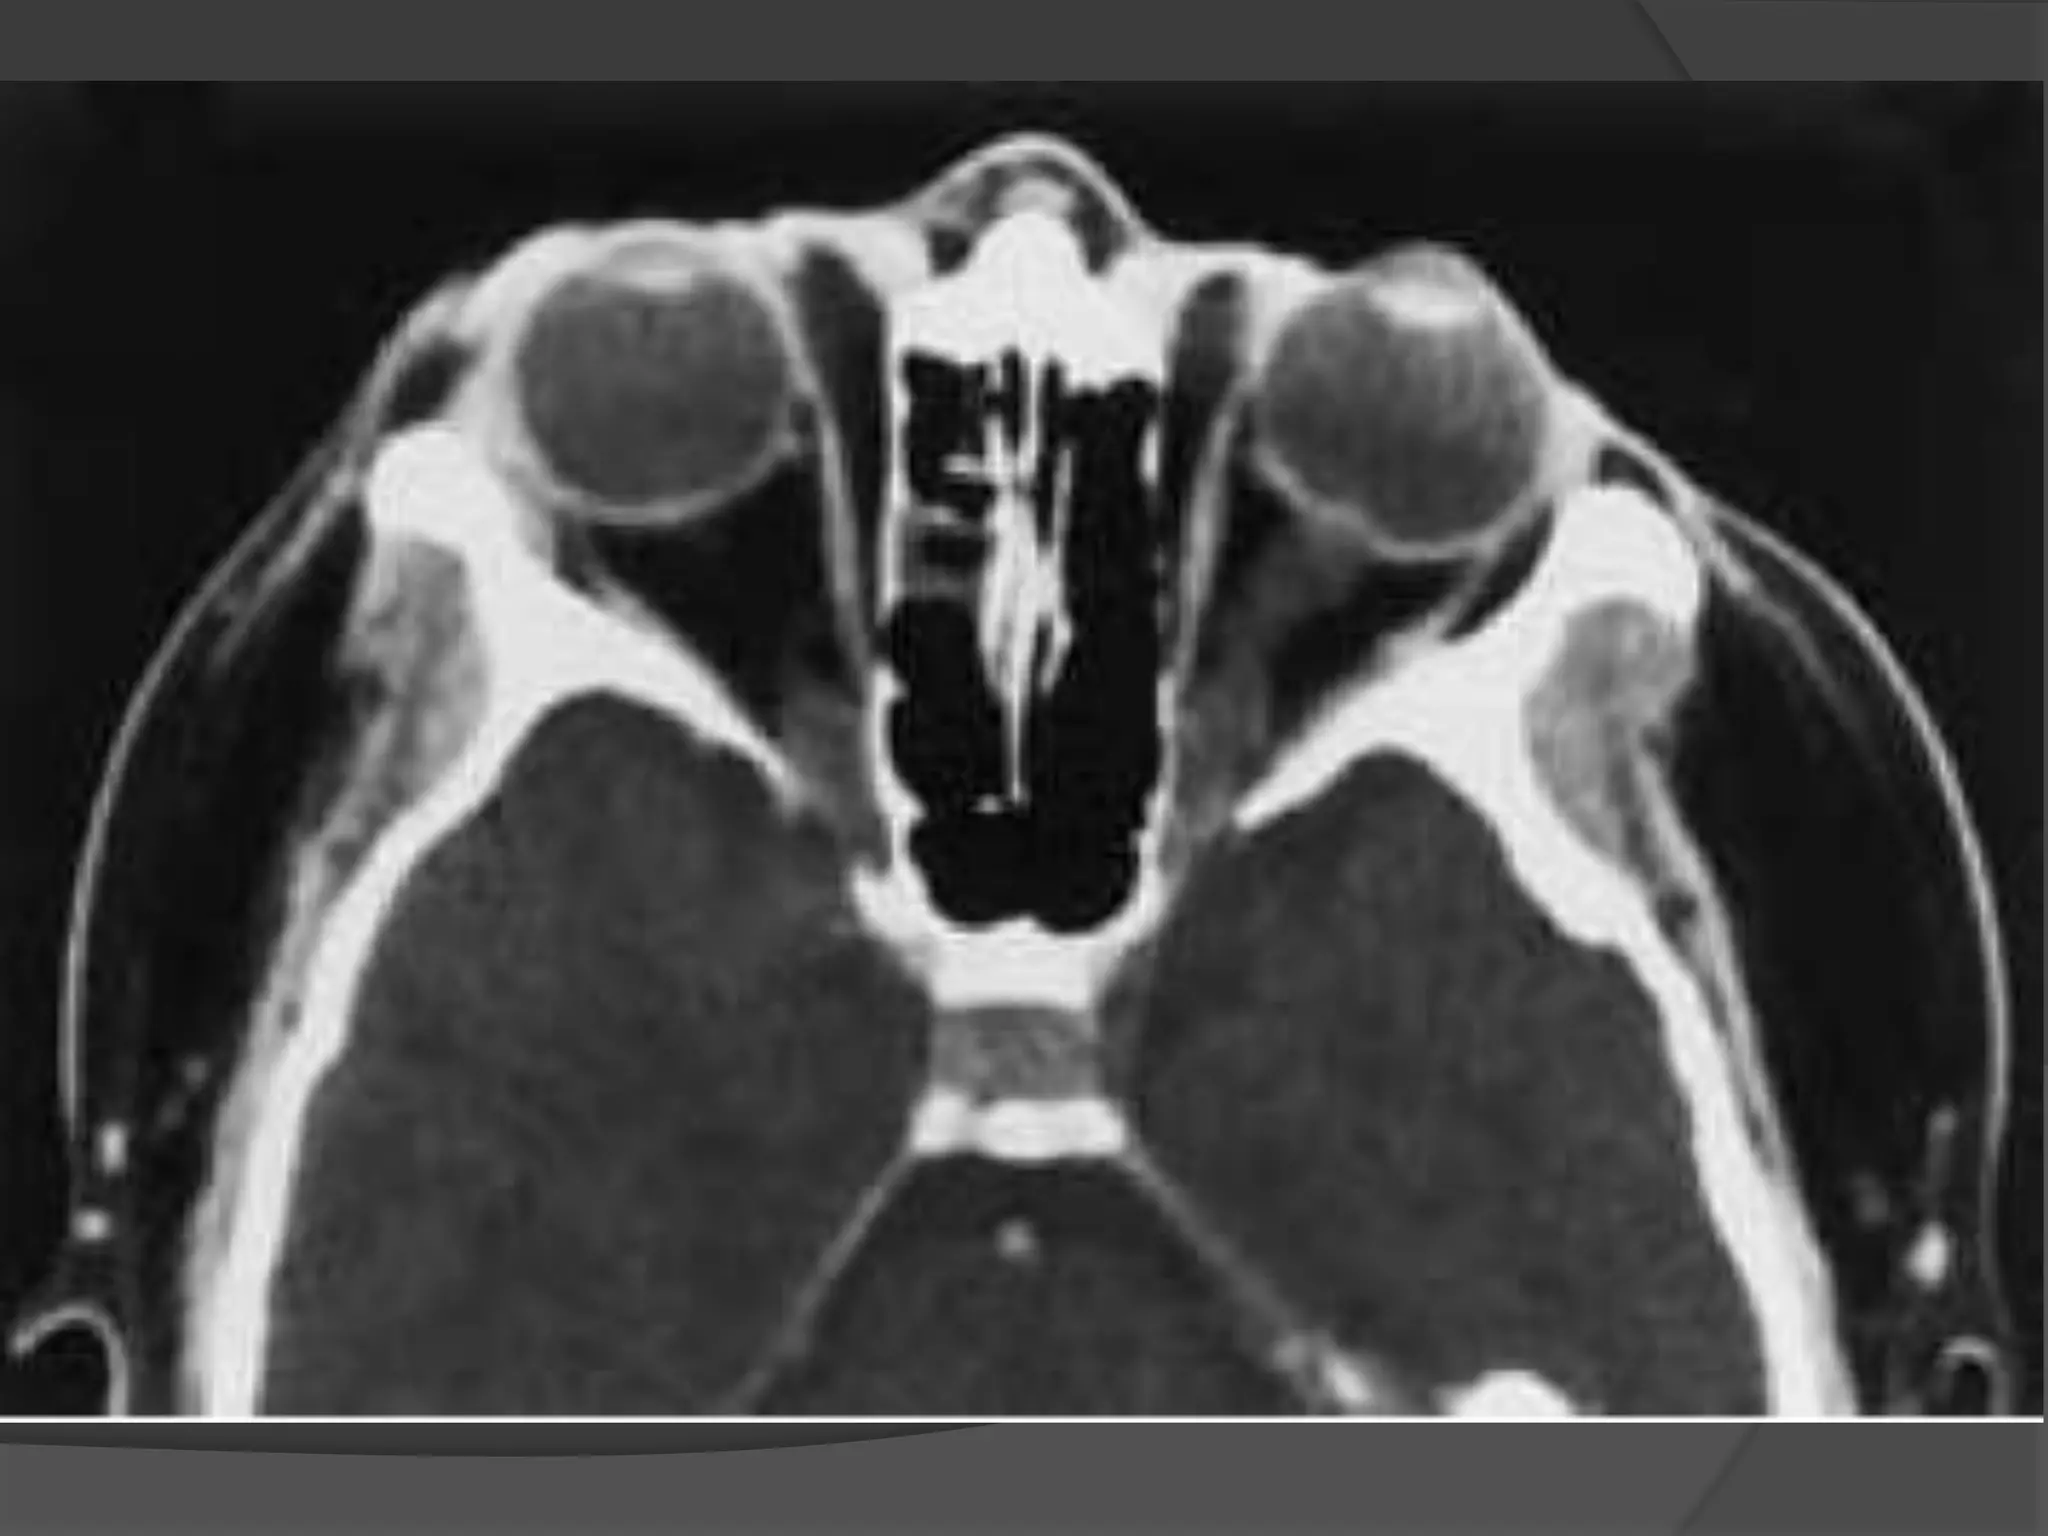

• #77 Scleral buckle in retinal detachment. A to D, Axial CT images showing the linear radial density encircling the globe (arrows). Note that if followed on all images, the radiodensity makes a complete ring around the globe.